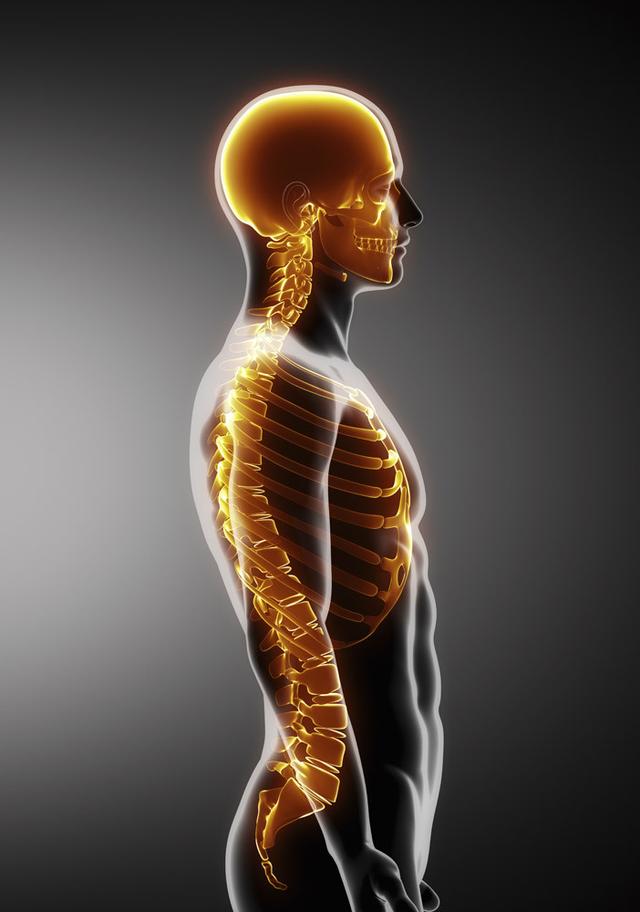

从一方面来说,人类是弱小的,容易生病,容易受伤,但从另一方面来说,人类也是强大的...